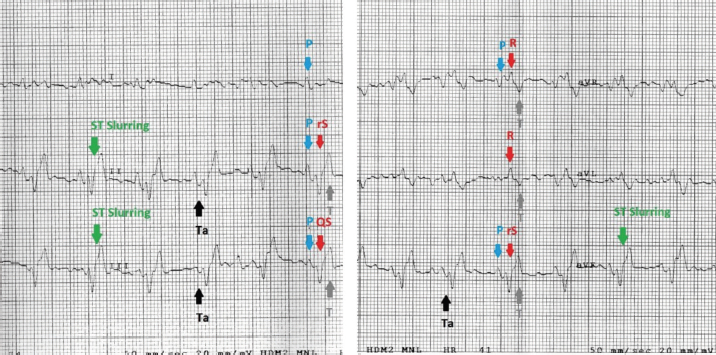

Fig. 2. Examples of mandarin duck ECG. Sinus rhythm, heart rate of 200 beats per minute with regular RR intervals. Lead I appears mostly isoelectric except for positive P waves, which are oriented downward and to the left. The P wave is often followed by the Ta, particularly clearly visible in II, III, and aVF. The QRS complex appears negative with rS or QS morphology in the lower leads; the vector is oriented mostly upward and slightly to the left. ST slurring is visible only in some beats, although the ST section always remained very short.

Table 1 summarizes the recorded morphological parameters. P wave was mainly positive in leads II, III, and aVF, while they were negative in aVR presenting a great variability in lead I. The QRS complex was mainly isoelectric in lead I and negative with rS or QS morphology in leads II, III, and aVF. It was positive with R pattern in aVL, while it was negative or positive with QS or R morphology, respectively, in aVF. T waves were mostly positive in leads II, III, and aVF. They were negative in aVL and aVF and isoelectric in lead I. The Ta wave was detected in 8/10 ducks, while only 2/10 ST slurring was observed. The vast majority of ECG traces were obtained without major artifacts. However, in a few points of the recorded ECG traces, movement (large swing in the baseline) and tremors (narrow and rapid spikes in the baseline) artifacts were visible. A regular sinus rhythm was observed in all birds.

Table 2 summarizes the amplitude and duration parameters of the recorded ECG parameters in II limb lead. The heart rate ranged between 160 and 380 beats/minute (mean=246; SD ± 90; 95% CI=190.22–301.78). The duration of the P wave ranged between 20 and 40 milliseconds (mean=25.2; SD ± 6.5; 95% CI=21.17–29.22), and the amplitude was between 0.06 and 0.16 mV (mean=0.11; SD ± 0.03; 95% CI=0.09–0.12). The QRS duration ranged between 24 and 80 milliseconds (mean=46.4; SD ± 15.7; 95% CI=36.66–56.13). The duration of the T wave was between 36 and 44 milliseconds (mean=39.2; SD ± 2.52; 95% CI=37.63–40.76), while the amplitude ranged between 0.11 and 0.52 mV (mean=0.28; SD ± 0.15; 95% CI=0.18–0.37). The duration of PQ/PR interval ranged between 40 and 60 milliseconds (mean=50.4; SD ± 8.04; 95% CI=45.41–55.38). The ST segment was very short with a duration between 4 and 20 milliseconds (mean=15.3; SD ± 6.11; 95% CI=11.51–19.08). The duration of the QT segment was between 96 and 144 milliseconds (mean=115.2; SD ± 16; 95% CI=105.28–125.11). In all ducks examined, the MEA on the frontal plane was between −104° and −71° (mean=−88.84; SD ± 9.57; 95% CI=−90.73 to –78.86). Figure 2 show examples of a mandarin duck ECG trace.

ST slurring, or the fusion of the QRS complex with the T wave and, therefore, absence of the ST segment, has been recorded several times in the past in various bird species with highly variable percentages (Lopez Murcia et al., 2005; Hassanpour and Khadem, 2013; Kaya and Soylu, 2013; Kaya and Çenesiz, 2018). Also, in the mandarin ducks, the ST tract is often very short, and in 2/10 cases there was a real ST slurring.